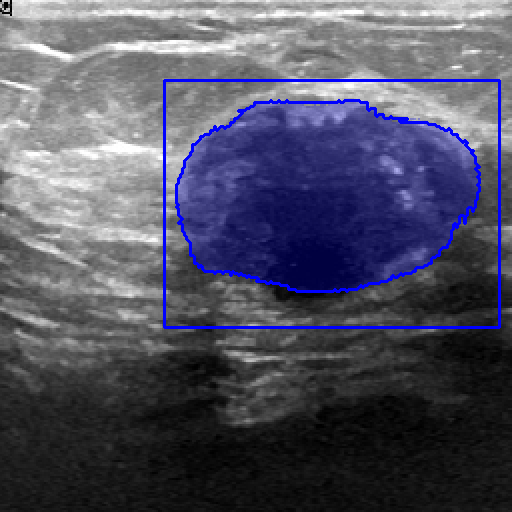

| Fine-Tuning | BUID [70] | 2D Ultrasound | 647 | Breast Cancer Segmentation | ||

| Method | ISIC-2018 (Skin Lesion) | JSRT (Lung X-ray) | KvaSir (Polyp) | Drive (Vessel) | BUID (Breast Cancer) | |

|---|---|---|---|---|---|---|

| Randomly (R50) | 86.16 0.14 | 93.10 0.12 | 62.85 1.32 | 59.82 2.00 | 65.54 0.21 | |

| Pre-trained ImageNet [60] | 86.87 0.47 | 94.52 2.66 | 83.85 1.32 | 65.12 1.55 | 72.64 1.14 | |

| Attention-Unet [77] | 86.81 0.51 | 94.47 2.71 | 82.23 1.41 | 65.02 1.44 | 72.19 1.16 | |

| U-Net ++ [78] | 86.71 0.49 | 94.32 2.81 | 82.23 1.41 | 65.38 0.78 | 73.76 2.83 | |

| 2D Supervised Method | Trans U-Net [76] | 86.60 0.82 | 89.80 0.35 | 67.11 0.24 | 62.63 0.24 | 67.90 0.40 |

| Twin-Barlon [13] | 86.01 0.07 | 94.56 3.09 | 83.00 0.23 | 65.73 1.46 | 74.46 1.19 | |

| Dino [79] | 86.79 0.09 | 94.84 2.79 | 79.84 1.62 | 65.39 0.81 | 76.21 0.57 | |

| SimCLR [15] | 87.28 0.21 | 94.79 2.93 | 82.20 0.51 | 65.22 2.18 | 76.52 0.22 | |

| Moco-v2 [17] | 87.24 0.14 | 94.05 3.52 | 78.24 1.35 | 64.92 2.21 | 75.93 1.96 | |

| Deepcluster-v2 [20] | 86.73 0.42 | 94.79 2.89 | 82.69 0.75 | 64.14 0.92 | 76.33 0.99 | |

| VicRegl [14] | 86.27 0.33 | 94.39 3.25 | 81.93 0.48 | 66.17 0.27 | 75.29 0.64 | |

| 2D-SSL on medical | LVM-Med (R50) | 87.76 0.30 | 95.13 2.64 | 86.76 0.94 | 66.97 0.27 | 78.65 0.72 |

| Clip [3] | 85.98 0.19 | 89.00 1.08 | 72.63 0.37 | 63.01 0.36 | 70.43 0.24 | |

| Flava [5] | 86.42 0.10 | 90.08 0.20 | 69.47 0.05 | 61.09 0.45 | 67.54 1.17 | |

| SAM [6] | 88.17 0.30 | 90.68 0.40 | 70.75 0.60 | 64.04 0.41 | 73.07 0.66 | |

| Foundation Model | LVM-Med (SAM’s ViT) | 88.41 0.28 | 90.74 0.47 | 73.10 0.08 | 65.49 0.12 | 77.20 0.42 |

| SAM (fixed encoder) [9] | 92.42 0.12 | 92.89 5.24 | 89.37 0.57 | 59.74 0.63 | 87.63 0.67 | |

| SAM with Prompt (no-train) [6] | 55.78 0.66 | 61.97 4.48 | 80.77 0.19 | 15.12 0.24 | 78.44 1.01 | |

| Prompt-based Seg. | LVM-Med (SAM’s ViT) | 92.48 0.07 | 93.74 4.06 | 90.09 0.14 | 63.01 0.02 | 89.69 0.61 |

In 3D settings, we segment 2D slices and merge results for a 3D volume. We also benchmarked with 3D self-supervised methods from [86]. Tables (2) and (3) show that our two versions with ResNet-50 and Sam’s ViT hold the best records in each category. For instance, we outperform 2D SSL methods trained on the same dataset, surpassing foundation models such as SAM, Flava, and Clip. In the prompt-based settings, LVM-Med also delivers better performance compared with SAM. Second, LVM-Med achieves the best overall results on seven of eight segmentation tasks, mostly held by LVM-Med with ResNet-50. The improvement gaps vary on each dataset, for e.g., from on Kvasir and BUID compared with 2D supervised methods.